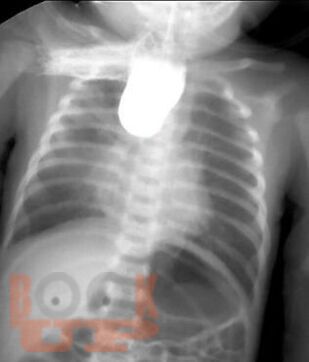

Диагностика и лечение хирургических заболеваний новорождённых и детей грудного возраста

В пособии рассматриваются современные принципы диагностики и лечения хирургических заболеваний новорождённых и детей первого года жизни, возможных осложнений и исходов. Акцентируем внимание студентов на эмбриогенез, этиологию и патогенез, классификацию, клинические проявления и выбор методов лечения. Пособие содержит вопросы для самоконтроля и список литературы для дополнительного изучения.